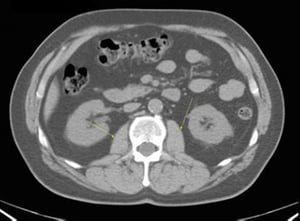

CT-Scan von Abdomen und Becken mit normaler Anatomie ohne Kontrastmittel (Folie 13)

1 = V. mesenterica superior; 2 = A. mesenterica superior.

© Springer Science+Business Media